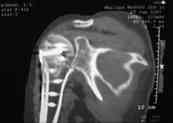

закрытый оскольчатый перелом проксимального отдела левой плечевой кости со смещением отломков (b1_xr.jpg). 06.04.2007 оперирована в одном из отделений: открытая репозиция, накостный остеосинтез проксимального отдела левой плечевой кости. Выписана с заключительным диагнозом: а)основной: закрытый 4-х фрагментарный (по Ниру) перелом проксимального отдела левой плечевой кости, со смещением отломков; б) осложнения основного: нейропатия левого локтевого нерва; в) сопутствующий: миокардитический миокардиосклероз ХСН 0-1.

В момент осмотра: нормостеническая конституция, по передней поверхности плечевого сустава – рубец. Рука в положении приведения. Отведение не более 10 град, дальнейшие движения с лопаткой до 20-25 град. Амплитуда сгибания-разгибания 10-15 град. Ротация отсутствует. Пальпаторно - выраженная болезненность над суставом, особенно в проекции клювовидного отростка. При попытках пассивных движений – боль. Рентгенограммы и результаты КТ приложены(b2(3)_xr.jpg, b1(6)_ct.jpg).

Диагноз: неправильно сросшийся в условиях накостного остеосинтеза оскольчатый перелом головки левой плечевой кости (11-С3.2), асептический некроз головки плечевой кости, смешанная артро-миогенная контрактура левого плечевого сустава; демиелинизирующая нейропатия левого локтевого нерва.

Анализ ситуации позволяет считать, что основными причинами контрактуры являются неправильная репозиция фрагментов головки (разворот кверху и кзади), асептический некроз головки плечевой кости (отчетливое склерозирование на СТ).